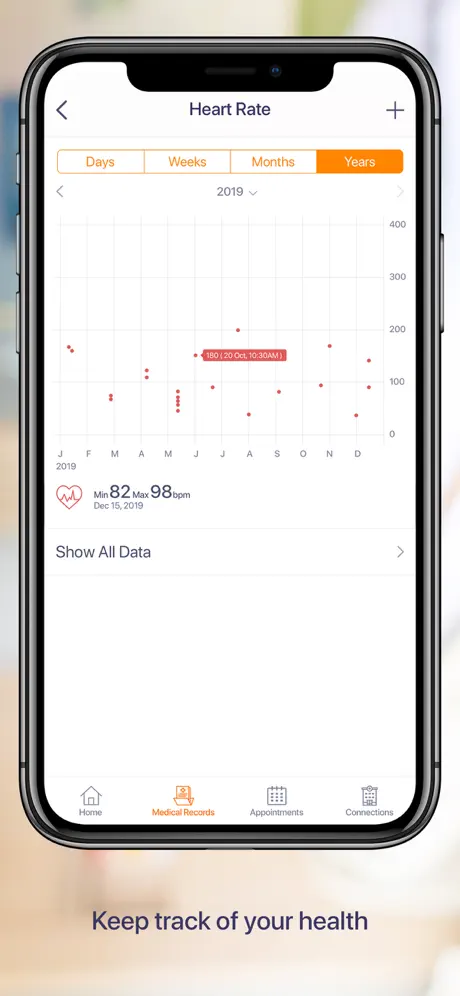

La aplicación permite a los pacientes acceder de forma segura a sus datos médicos o proxies familiares, programar citas, ver imágenes médicas, informes clínicos y de laboratorio de diferentes proveedores con la capacidad de descargar, archivar y compartir utilizando la tecnología de computación móvil más avanzada.

- Acceso fácil y rápido a los datos de su salud

- Conecte con sus dispositivos usables o ingrese sus datos médicos manualmente

- Integración con HealthKit para recuperar los signos vitales del usuario para compartir con los médicos de la instalación